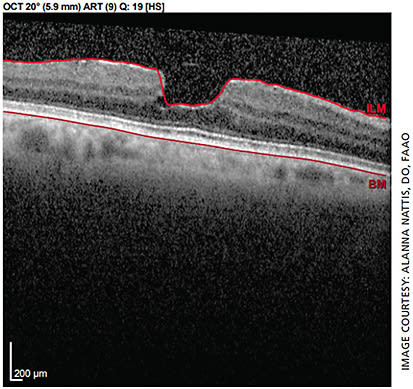

The patient is a 70-year-old healthy female with unremarkable preoperative exam in the right eye, mild epiretinal membrane (ERM) noted in the left (Figure 1). She states she desires spectacle independence post-cataract surgery.

However, due to presence of ERM in the left eye, the surgeon should be wary of choosing an IOL with a diffractive technology, as this could further degrade vision, decrease contrast sensitivity and lead to a suboptimal result.1,6,15,20,21 The conservative way of managing this: Use a monofocal IOL in the left eye — though the patient may not feel she is as “free” from spectacles as she would like.1,6,21,22 This should be communicated to the patient prior to surgery so that her expectations are on par with the surgical plan.

Another option is a non-diffractive extended depth of focus (EDOF) IOL in the left eye, such as Vivity (Alcon). This lens is designed to perform similarly to a monofocal in terms of contrast sensitivity and visual aberrations with expanded visual range.6,9,12,23